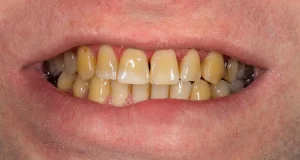

Dental Diseases & Conditions

Can You Drink Alcohol After a Tooth Extraction? (9 Safety Tips)